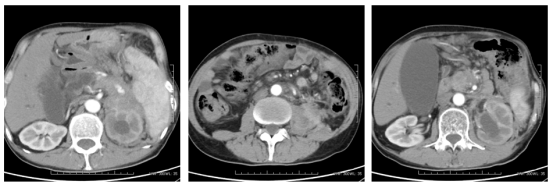

2024-03-20复查腹部CT:结肠脾曲术后,脾曲局部肠壁增厚,考虑结肠癌复发可能。肝多发转移,较前增多增大,胰腺区,左肾前,脾内侧及左侧肾上腺区及周围多发转移较前增大,肝门区,肠系膜内及腹膜后淋巴结较前增多增大,腹膜后淋巴结较前增多增大。评效疾病进展(PD)。

image.png

图4 2024年3月20日检查结果